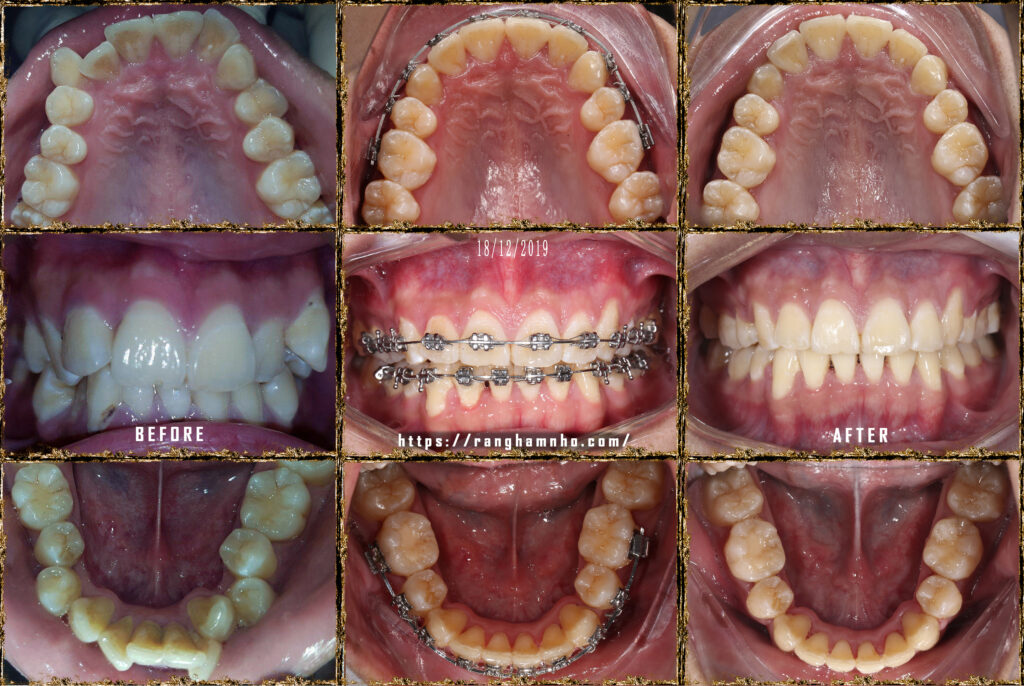

Bệnh nhân nam sinh năm 1998. Khớp cắn hạng I, với chen chúc và khấp khểnh nặng ở cả 2 hàm trên và dưới.

Cung hàm trên và cung hàm dưới đều hẹp, răng thiếu chỗ nghiệm trong.

Kế hoạch: Nhổ 4R4, chỉnh nha phân đoạn

Làm phẳng mặt phẳng cắn bằng cung tiện ích TMA 17×25 hai hàm